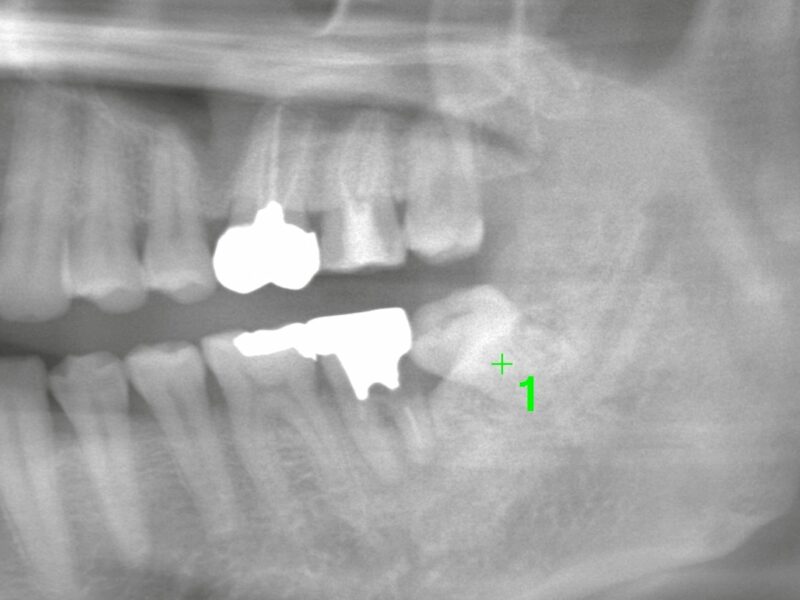

特徴4高精度診断を可能にする「歯科用CT」 -